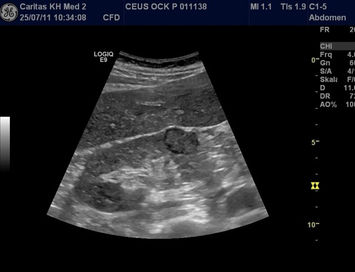

Galerie